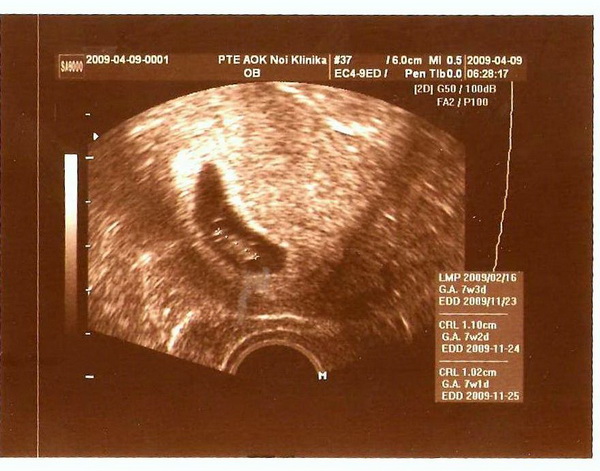

Sziasztok Elnézést csak még mindig sok a melo,de gondoltam gyorsan mesélem a hireket.... uh-n minden renben volt hallottuk a pici szivhangják. 11mm -res .Mindenki vigyázzon magára majd jövök Sziasztok Kép

Kata,

ne aggódj a méretek miatt. 7 hetesen 7 mm tökéletes. Levi is annyi volt, aztán most már 30 cm környékén jár :lol: